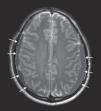

Hematoma subdural bilateral secundario a punción lumbar diagnóstica

Bilateral subdural hematoma after diagnostic lumbar puncture